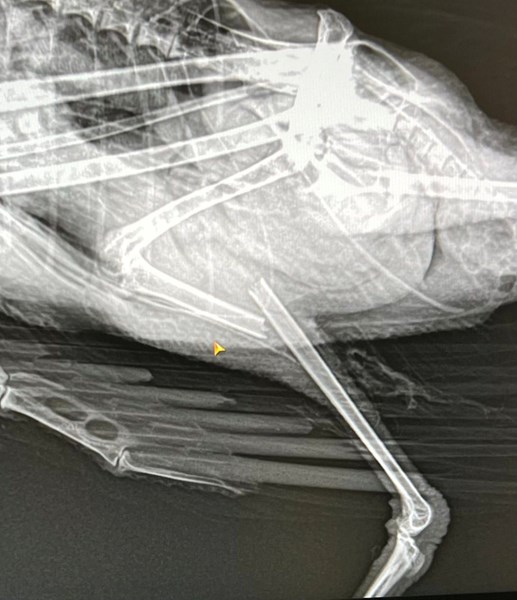

Бебето чайка, което намерих със счупено краче преди месец, направи първите си стъпки на открито днес.

Благодаря на д-р Гавазов, който му постави титаниев имплант. Той се погрижи добре за птичето и дори му даде име – Дунав Гълъбунов